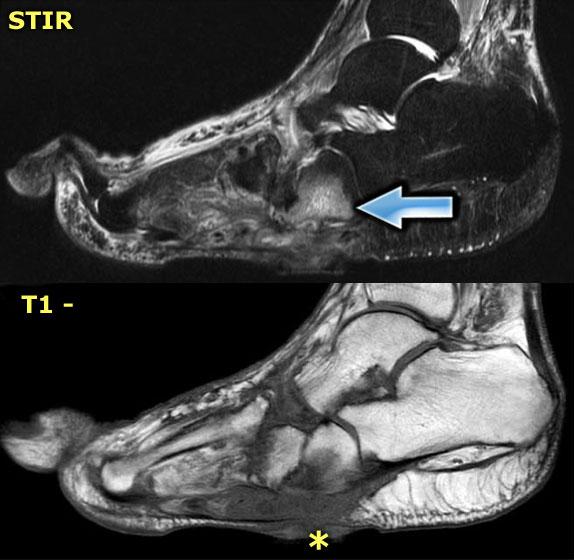

Đây là hình ảnh MRI của một bệnh nhân bị bệnh xương khớp thần kinh Charcot cấp tính.

Phù tủy xương thường không giới hạn ở một hoặc hai xương, mà xuất hiện ở toàn bộ bàn chân giữa.

Phù tủy xương và sự ngấm thuốc của nó thường tập trung ở vùng xương dưới sụn, gợi ý bệnh lý khớp.

Mô dưới da tương đối bình thường và không có vết loét hay các dấu hiệu nhiễm trùng khác.